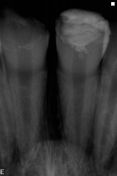

Si presenta alla nostra osservazione un bambino di 11 aa per un consulto in relazione agli elementi dentali 1.1 2.1 i quali in seguito ad un trauma avevano conseguito una frattura nella zona incisale di circa 1/3.

Il precedente odontoiatra, dopo diversi tentantivi di ricostruzione, aveva deciso di protesizzarli con corone provvisiorie in resina.

In seguito ad accertamenti clinici e diagnostici abbiamo deciso, soprattutto in realizzazione al fatto che il piccolo paziente necessita di un trattamento ortodontico, di ricostruire con stratificazione anatomica. I denti vengono lasciati vitali.

La lucidatura non viene effettuata per permettere l'adesione dell' attacco dell'apparecchio ortodontico.